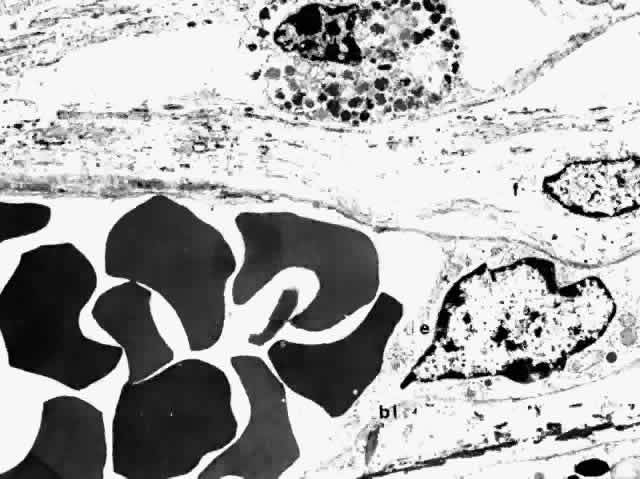

The walls of choroidal veins consist of an inner lining of endothelial cells, a media with a few irregularly and intermittently spaced smooth muscle cells, and a thin adventitia of fibrocytes and collagen fibers (Fig. 27). The structure of all the choroidal veins, including the vortex veins, is virtually identical. The endothelial lining is continuous. The largest veins have a diameter as large as 300 μm; and the smallest veins, including the postcapillary venules, are 10 to 40 μm in diameter. The endothelial cells of the choroidal venules have discontinuous zonulae occludentes (Fig. 28).53

Fig. 27. Thin-walled choroidal vein lined internally by endothelial cell (e) with its basal lamina (bl), and externally by a fibrocyte (f). Smooth muscle is not evident in this section. (× 4750)